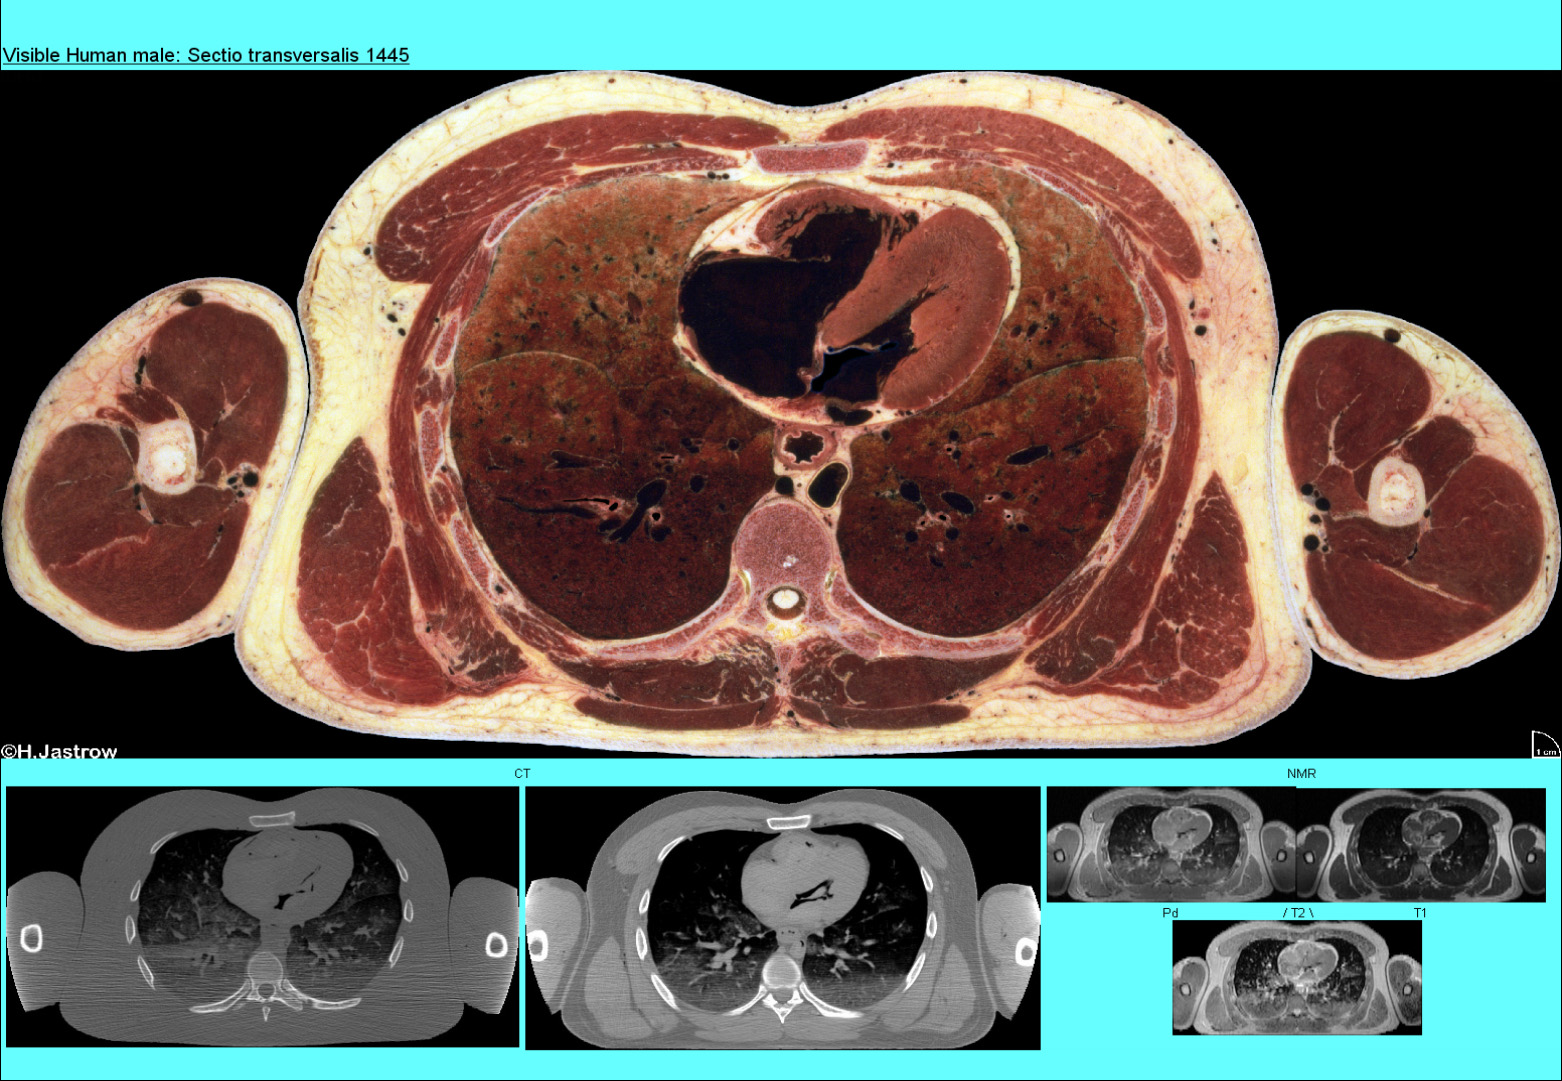

In Abb.27 sehen Sie eine Seite des Brustraums mit den zugehörigen CT und NMR Abbildungen. Man erkennt die beiden Herzkammern, den rechten Vorhof und die Lungen, die Wirbelsäule, Rippen und Muskeln der Oberarme.